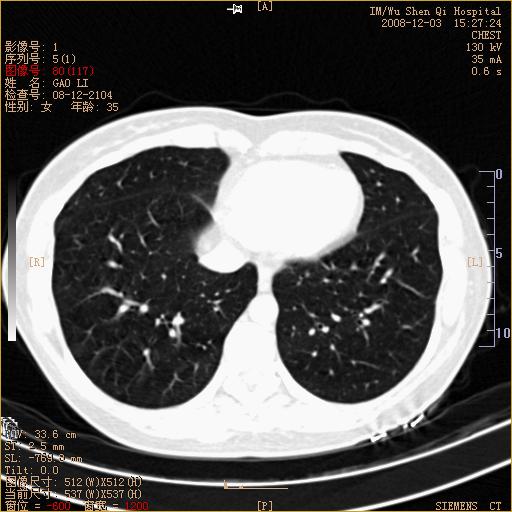

标题: CT16895:女,35岁,反复咳嗽数月,只传部分图像,是否考虑 [打印本页]

标题: CT16895:女,35岁,反复咳嗽数月,只传部分图像,是否考虑

左下肺支扩

典型“印戒征”。

印戒征,支持支扩.

左下肺扩支

印戒征,支扩